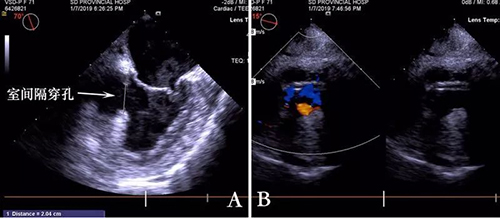

患者杨某某,71岁,入院诊断为“冠心病,心梗,室间隔穿孔”,入住心外科,超声发现:室间隔穿孔位于后间壁,直径20mm(图3)。年龄大,心功能差,开胸体外循环手术风险高,而介入方法又难以治疗。经科室讨论,选择外科介入封堵的方式是最佳的治疗方案,微创、不用体外循环、不接触X线和造影剂,更利于患者的救治。

图3